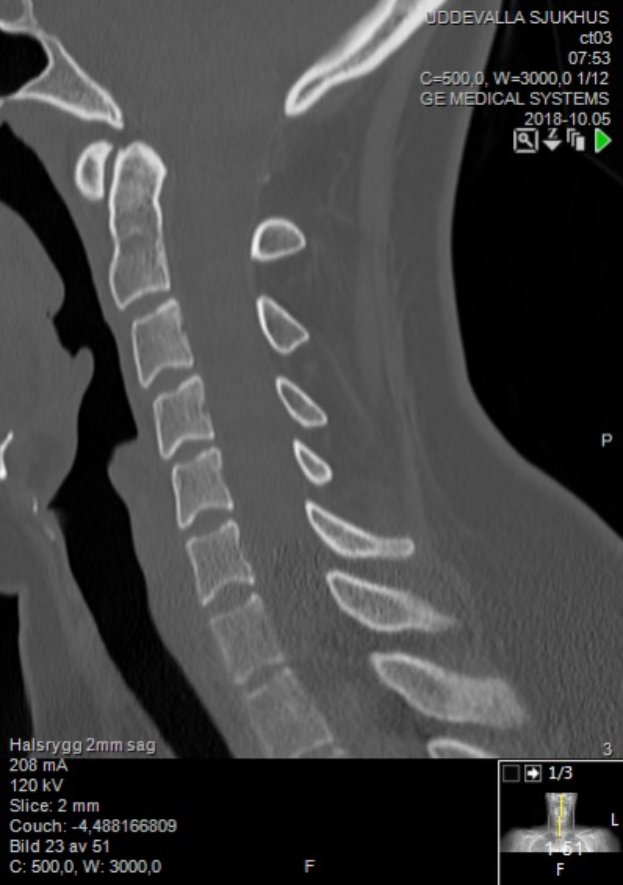

Ein Röntgenbild eines Mannes am Hals mit einem sichtbaren Bruch in der Mitte, das auf einem Computerbildschirm mit Text und Zahlen angezeigt wird.Julian Schmitz